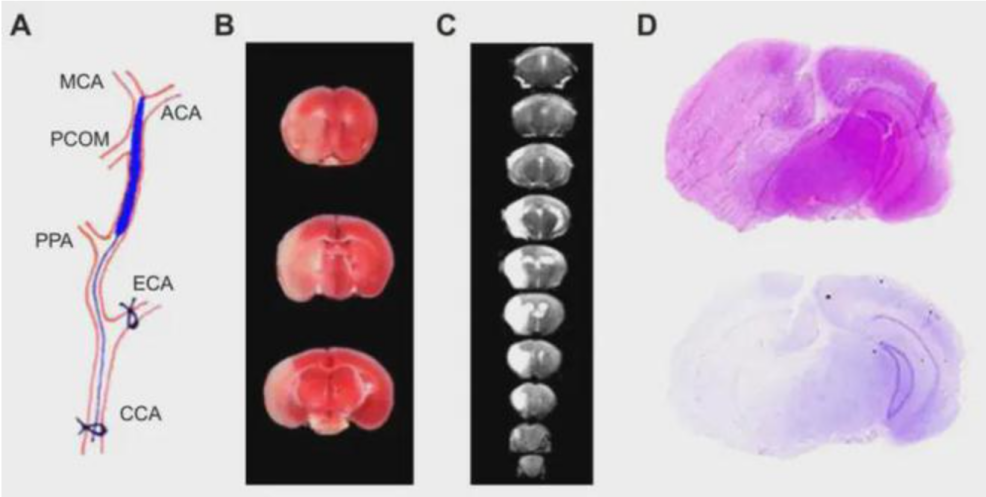

(1) 线栓栓塞法(MCAO模型)

原理:通过颈动脉插入栓线阻塞大脑中动脉(MCA),模拟血管栓塞。

操作步骤(以大鼠为例):

① 术前禁食12小时,麻醉后颈部备皮消毒;

② 分离颈总动脉(CCA)、颈外动脉(ECA)及颈内动脉(ICA);

③ 结扎ECA,在CCA分叉处切口,插入硅胶涂层的尼龙线栓(直径0.22-0.28mm);

④ 推进线栓至ICA颅内段(深度18-22mm),遇阻力表明到达MCA起始部;

⑤ 阻断血流60分钟后拔栓实现再灌注。

MCAO大鼠模型造模示意图

MCAO大鼠造模后脑组织形态变化示意图

- 影像学评估

- MRI:DWI序列检测早期梗死灶,T₂WI评估水肿范围;

- 组织学验证

- TTC染色:梗死区呈苍白色,计算梗死体积比(公式:梗死体积% = (对侧半脑体积 – 患侧正常组织体积) / 对侧半脑体积×100%);

- HE染色:观察神经元坏死、炎性浸润及出血灶形态。